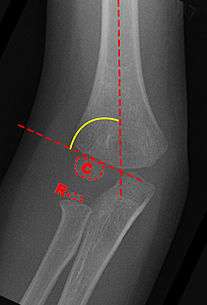

Baumann's angle , also known as the humeral-capitellar angle, is measured on an AP radiograph of the elbow between the long axis of the humerus and the growth plate of the lateral condyle.

Alteration of Baumann angle: Baumann's angle is created by drawing a line parallel to the longitudinal axis of the humeral shaft and a line along the lateral condylar physis as viewed on the AP image normal is 70-75 degrees, but best judge is a comparison of the contralateral side deviation of more than 5 degrees indicates coronal plane deformity and should not be accepted.